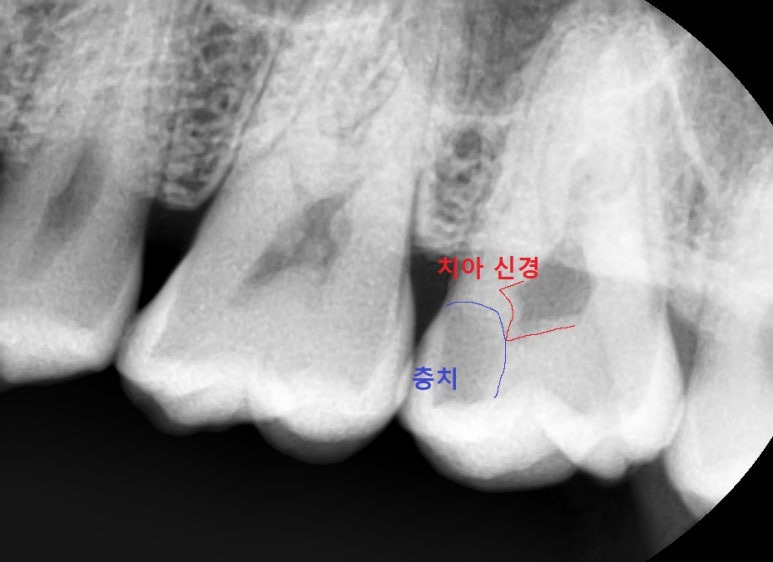

충치가 엑스레이상 치아신경과 맞닿아있는 경우

충치를 제거해보면 치아신경이 노출되는 경우가 많아

신경치료를 들어가게 되는 경우가 많습니다.